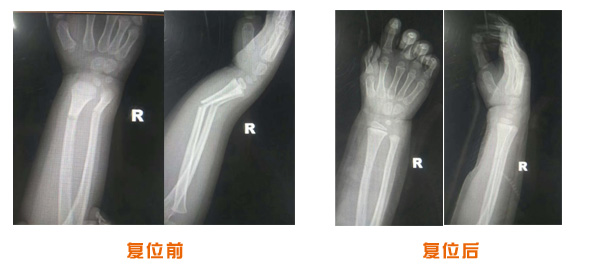

尺橈骨骨折治療前后

尺橈骨克雷氏骨折治療前后